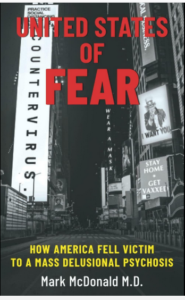

Psychiatrist Mark McDonald, M.D., author of United States of Fear: How America Fell Victim to a Mass Delusional Psychosis, sent a letter to his patients in February banning child masking in his practice. Forcing kids to mask, he says, is child abuse.

“My first ethical responsibility as a physician is to do no harm to my patients, and allowing children to mask their faces has caused and continues to cause tremendous harm to them physically, emotionally, psychologically and developmentally. Any argument to the contrary is naive and irrational.”

“Masks… may not leave physical scars (although they often result in painful skin infections that can lead to permanent facial disfigurement),” says Dr. McDonald, “but they do cause significant and possibly permanent damage to a child’s brain, retarding speech and language development, crippling social skills, and inciting a vicious cycle of emotional dysregulation leading to major depression, self-harm, and substance abuse. We would never allow someone to do this to our children directly, so why do we condone it through the vehicle of a facemask?”

In his post, Masking Children is Child Abuse, psychiatrist McDonald adds:

“Since children began wearing masks at school, on the athletic field, in airplanes—essentially everywhere outside the home—I have seen a significant decline in their ability to make eye contact, speak clearly, and initiate face-to-face communication with other human beings. Emotional resilience has dramatically declined. Children have become dull and slow in their thinking.”

And “with the advent of the mask craze, mental illness is no longer invisible in the public space,” says Dr. McDonald. “What was once reserved for only a psychiatrist’s ears is now on flagrant display to any citizen with eyes to see it.”

Psychiatrist Mark McDonald, MD, author of United States of Fear: How America Fell Victim to a Mass Delusional Psychosis, explains further:

“The fuel is fear. We cannot become mass delusionally psychotic without first being scared. The fear has been the driver behind this pandemic from the very beginning. Without fear, it all falls apart… An entire group, an entire population which is the American people, all at the same time, losing their rational faculties. Being unable to think, acting as a herd…

“It’s been the fear driven by government, corporations and the media all colluding together to perpetuate the mass delusional psychosis… The endpoint of this is the same as for every totalitarian regime throughout the 20th century—dependency on government. Once people depend on government, then they don’t depend on their families, they don’t depend on their churches, they don’t depend on their communities.”

Click for 29-minute video of interview with Dr. Mark McDonald, author of “UNITED STATES OF FEAR—How America Fell Victim to a Mass Delusional Psychosis”